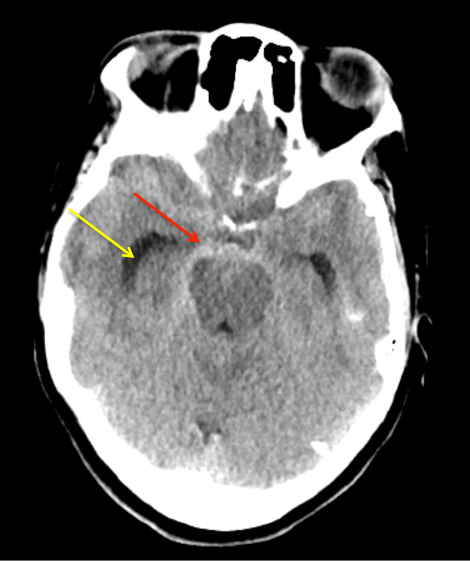

A man in his 40’s experienced an acute onset of a moderate headache. Over the next 3 days, his family noticed increased lethargy, decreased appetite, and gait imbalance, which prompted them to bring him to the ED for evaluation. Initial CT scan of the brain confirmed diffuse subarachnoid hemorrhage with hydrocephalous, which required emergent EndoVentricular Drainage for a progressive diminished level of consciousness, WFNS Grade 3-4 (Figure 1).

Figure 1: Non-Contrast CT of the Brain demonstrates diffuse subarachnoid hemorrhage(red) and early dilatation of the temporal horns consistent with hydrocephalous (yellow).